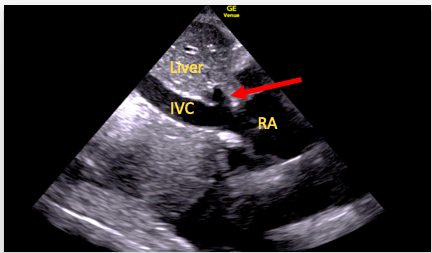

What is imaged though tilting the transducer in subcostal short axis? Sketch an image.

IVC/hepatic vein

RA

TV

Describe the Sniff test and its purpose.

Ask the patient to sniff to collapse the IVC

Measure the diameter of the IVC and its collapsibility index to assess RA pressure

Name the 3 views in subcostal SAX and describe the maneuvers to reach those views.

IVC, Hepatic veins

indicator towards pt head

angles right to the posterior aspect of the heart